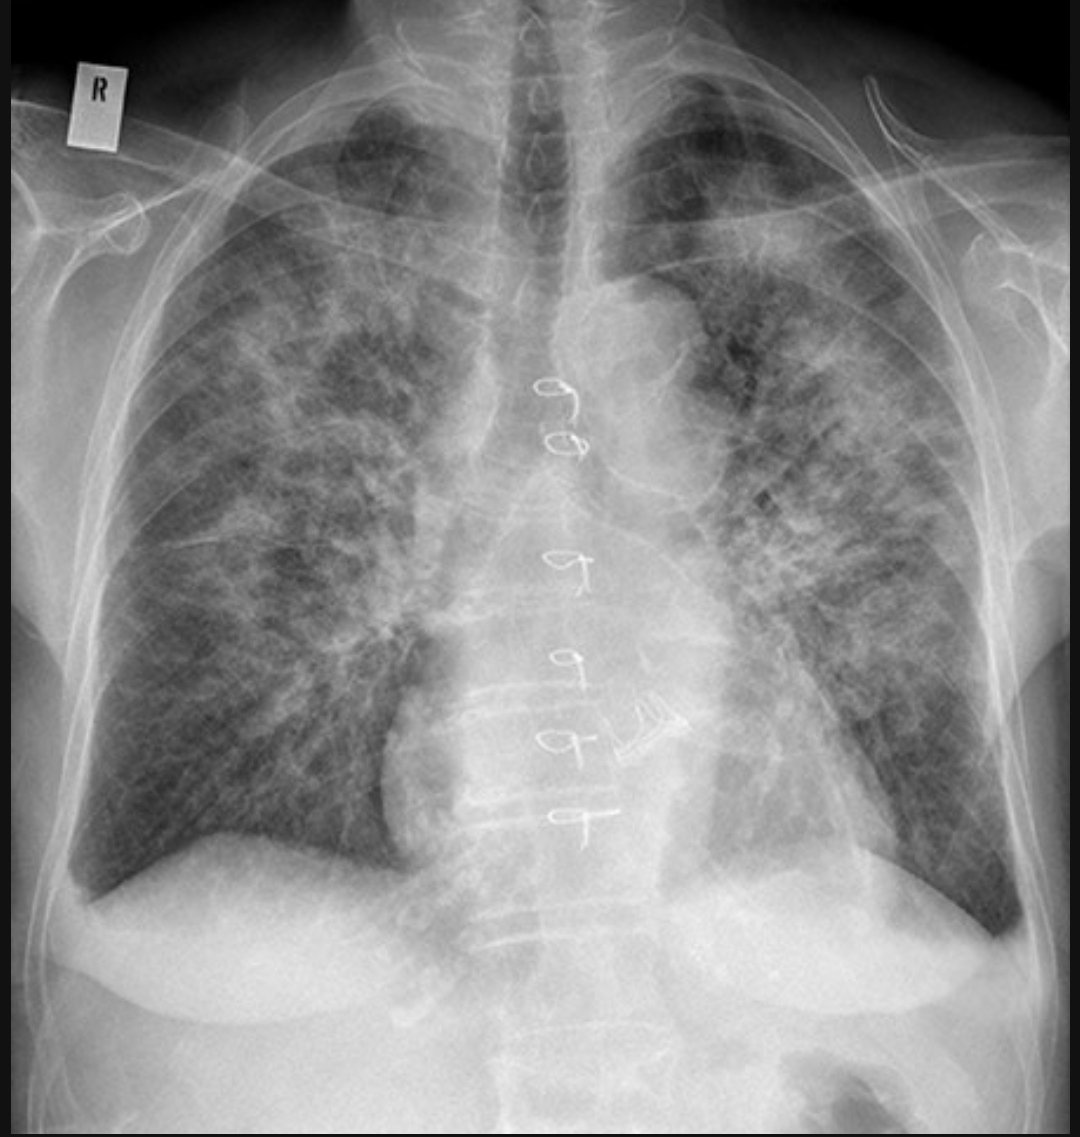

Acute shortness of breath....

Diagnosis? Image

Alveolar oedema - Bat's wing pattern

Alveolar oedema is caused by fluid leaking from the interstitial tissues into the alveoli and small airways, and manifests as airspace shadowing (consolidation)

In the context of acute pulmonary oedema, alveolar oedema radiates symmetrically from the hilar regions in a ‘bat's wing’ distribution of airspace shadowing Image